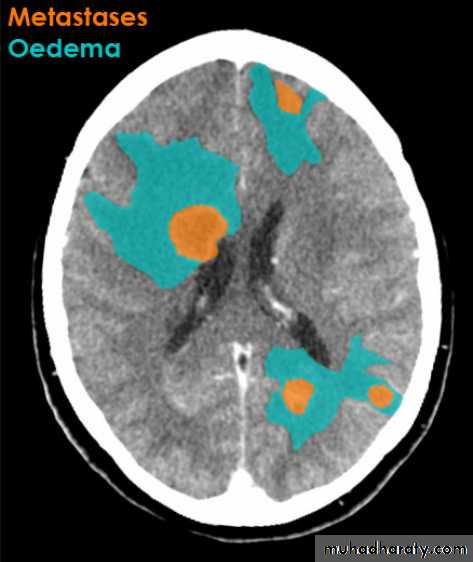

Secondary metastasis

Old age group above 50 Y , any lesion within the cerebellar hemisphere it is secondary metastasis unless proven otherwise F. from breast CA M. from bronchogenic CA .

Appear as nodular single or multiple lesion hypo dense or hyper dense .

Surrounded by per focal edema

Enhanced as solid or ring pattern of enhancement .